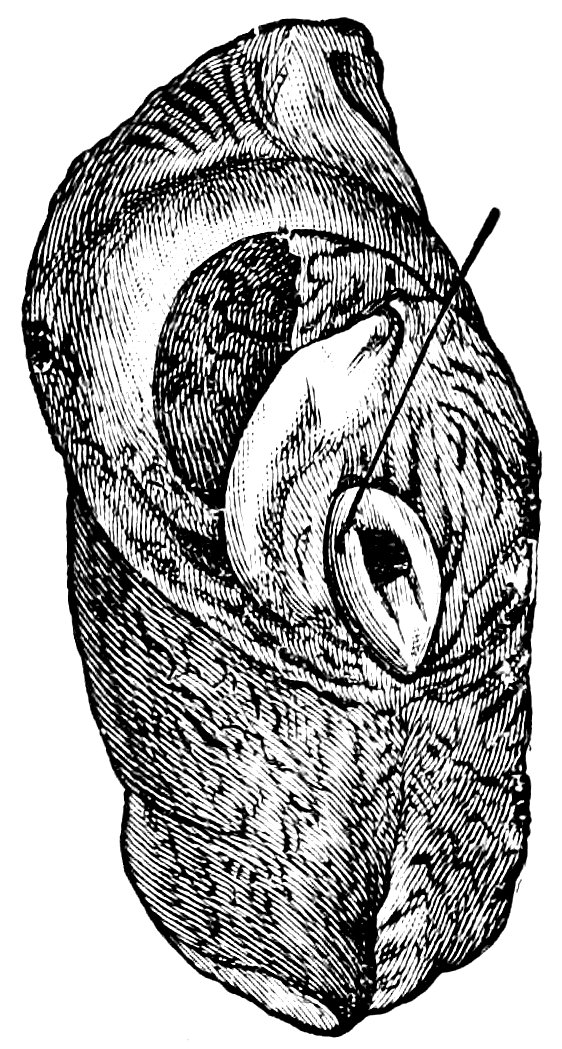

| 72. | Normal Shape of the Portio Vaginalis | 503 |

| 73. | Conoidal Shape of the Portio Vaginalis | 503 |

| 74. | “Apron-Shaped” Vaginal Portion, a. Greatly elongated anterior lip; b. Shorter posterior lip of the cervix | 504 |

| 75. | “Beak-Shaped” Vaginal Portion. Posterior aspect | 504 |

| 76. | Simple Hypertrophy of the Portio Vaginalis, which projected from the Vulva | 506 |

| 77. | Elongated Cervix, bent upwards | 506 |

| 78. | Cervical Polypus, originating from an Ovulum Nabothi | 510 |

| 79. | Ectropium in a Case of Bilateral Laceration of the Cervix (after A. Martin) | 514 |

| 80. | Anteflexio Uteri (after A. Martin) | 518 |

| 81. | Retroflexio Uteri (after A. Martin) | 520 |